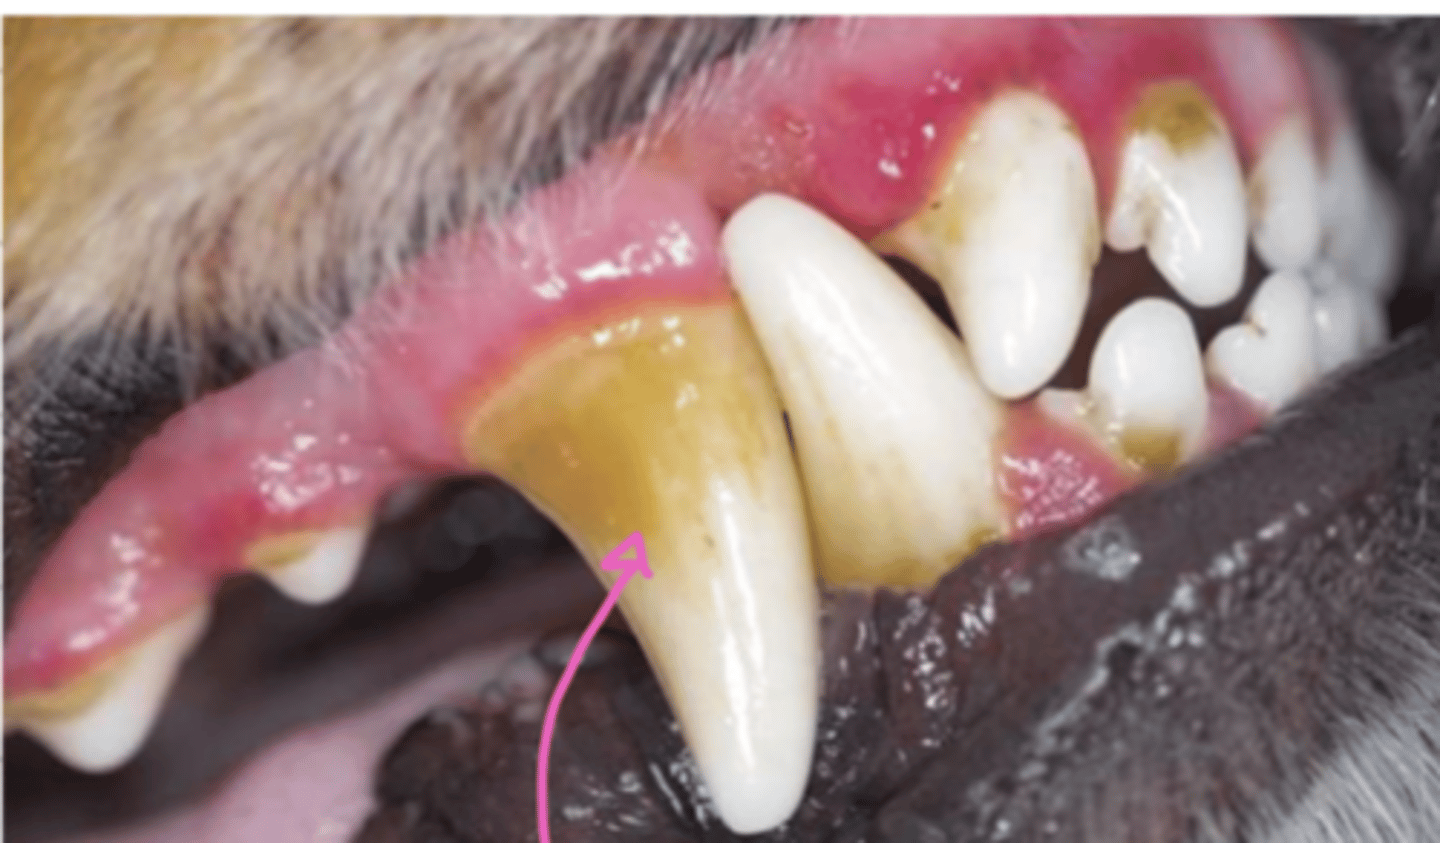

what is the common etiology of gingivitis in dogs?

gingivitis

small dogs commonly have _______ because of tartar

gingivitis (due to tartar)

what problem does this dog have?